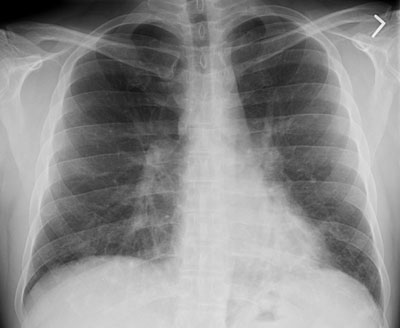

Bronchiolitis obliterans with organizing pneumonia (BOOP) is a histologic description and not a specific diagnosis. BOOP represents a proliferative bronchiolitis associated with organizing pneumonia in the surrounding lung parenchyma.

BOOP presenting with pulmonary nodules

BOOP case 2

Cryptogenic Organizing Pneumonia